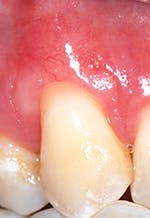

Secondly, gently retract the patient's lip or cheek to gain access, place the periodontal probe on the outside of the tissue, and measure from the gingival margin to the mucogingival junction, and record (see Figure 3).

Thirdly, measure the clinical probing depth (pocket depth to the sulcus) (see Figure 4). To calculate the attached gingiva, subtract the probing depth from the outside measurement of the gingiva for the total width of of attached gingiva. Record the width of the attached gingiva and identify any teeth that need tissue regeneration, such as root coverage surgery (see Miller classification I-III, Table 1).

Report to the dentist any teeth with recession that also have loss of attached gingiva width of less than 2 mm to indicate that root coverage surgery is recommended.